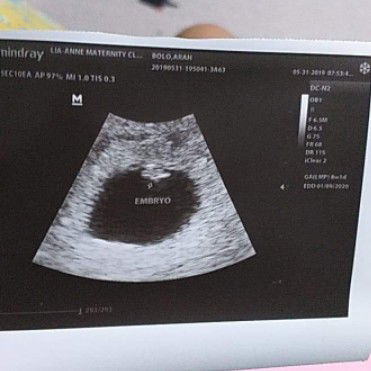

Hello mga Momshie.. ako ung nag tanung nung nkraang araw kung talaga bang pregnant ako hehe.. ast sinunod ko po lahat ng sinabi nyo.. nag punta na ako sa OB at nag pcheck up tpos nag pa transV po ako.. and charan .. 6w and 3days na sya.. un lang magkaiba sa bilang kapag sa unang araw ng huling regla ko ang sinunod.. kasi pag sa last regla ko ang bilang 2months na pi ako preggy pero sa TransV lumalabs 6w3D palang po.. okay naman po ang lahat at may heartbeat na si baby at okay naman daw po at normal..